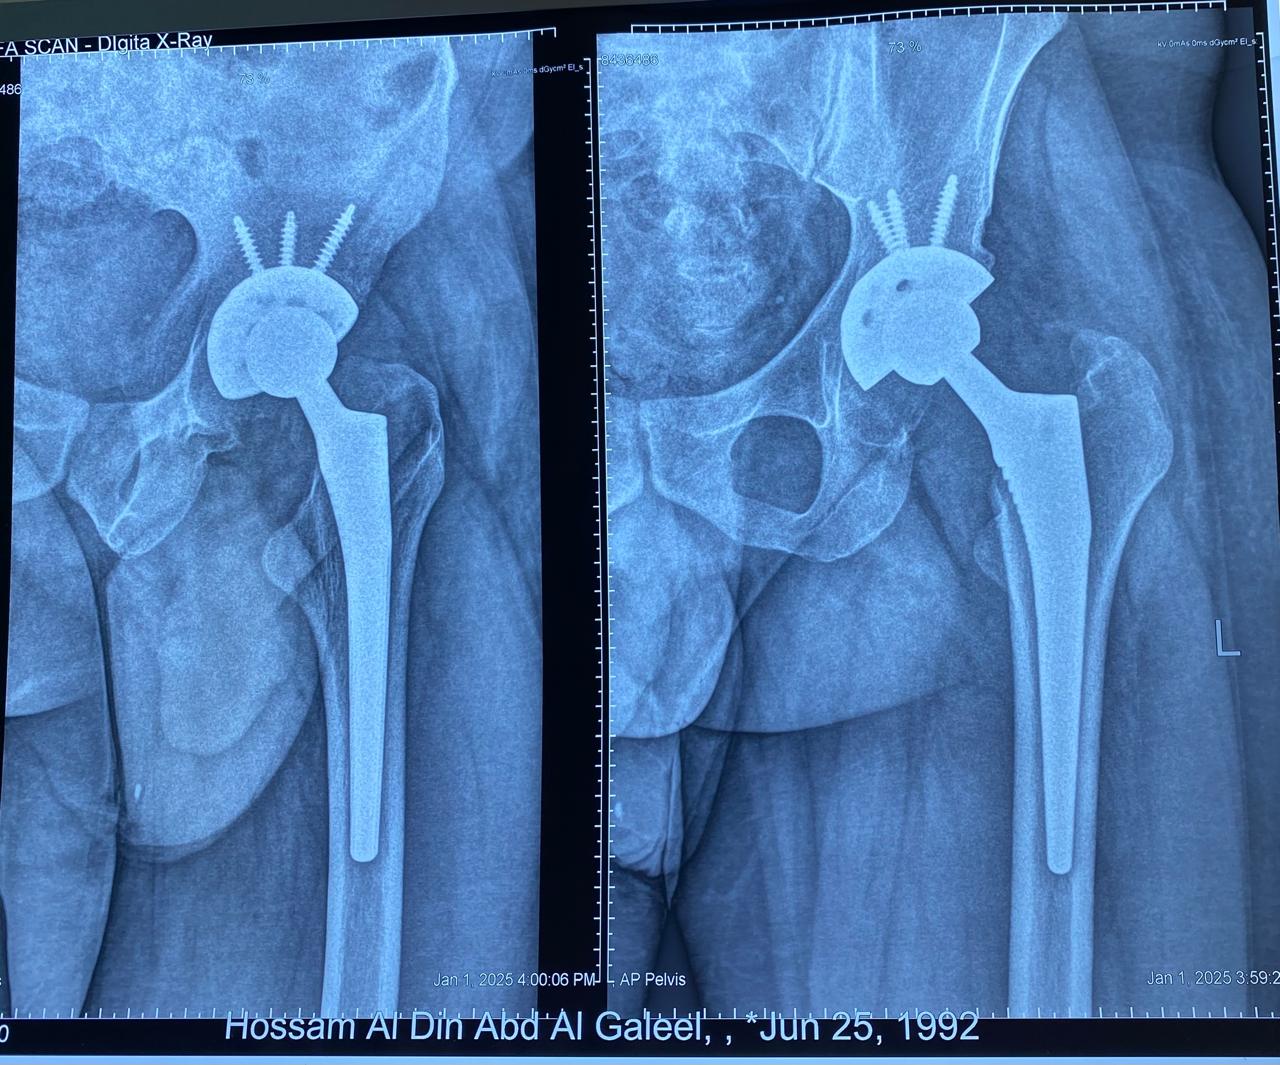

حسام الدين عبدالجليل

٣٠ عاما

يعاني من تاكل شديد منذ الطفولة في مفصل الحوض الأيسر.